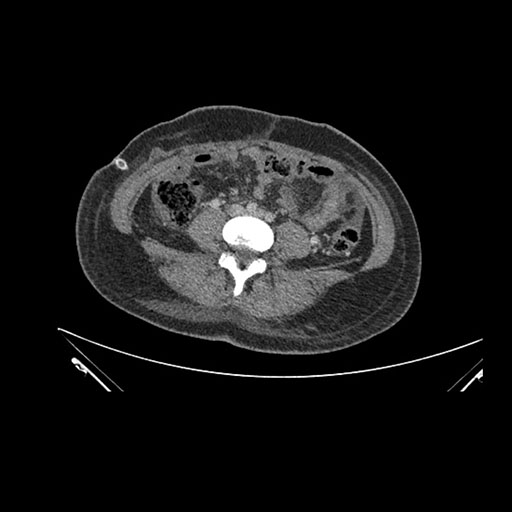

Look through the patient's CT scan to identify any areas of concern for the necessary procedure.

Axial Arterial

Axial Venous

Imaging analysis

Based on initial findings, which issue(s) would you be most concerned about?